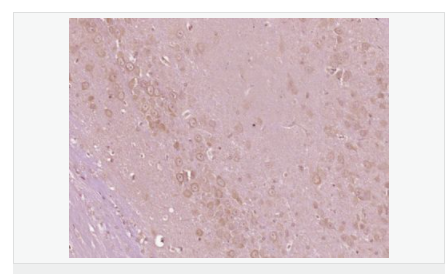

| 产品应用 | ELISA=1:5000-10000 IHC-P=1:100-500 IHC-F=1:100-500 IF=1:100-500 (石蜡切片需做抗原修复) not yet tested in other applications. optimal dilutions/concentrations should be determined by the end user. |

| 产品介绍 | This gene encodes a cytoplasmic protein tyrosine kinase which is involved in calcium-induced regulation of ion channels and activation of the map kinase signaling pathway. The encoded protein may represent an important signaling intermediate between neuropeptide-activated receptors or neurotransmitters that increase calcium flux and the downstream signals that regulate neuronal activity. The encoded protein undergoes rapid tyrosine phosphorylation and activation in response to increases in the intracellular calcium concentration, nicotinic acetylcholine receptor activation, membrane depolarization, or protein kinase C activation. This protein has been shown to bind CRK-associated substrate, nephrocystin, GTPase regulator associated with FAK, and the SH2 domain of GRB2. The encoded protein is a member of the FAK subfamily of protein tyrosine kinases but lacks significant sequence similarity to kinases from other subfamilies. Four transcript variants encoding two different isoforms have been found for this gene. [provided by RefSeq, Jul 2008] Function: Non-receptor protein-tyrosine kinase that regulates reorganization of the actin cytoskeleton, cell polarization, cell migration, adhesion, spreading and bone remodeling. Plays a role in the regulation of the humoral immune response, and is required for normal levels of marginal B-cells in the spleen and normal migration of splenic B-cells. Required for normal macrophage polarization and migration towards sites of inflammation. Regulates cytoskeleton rearrangement and cell spreading in T-cells, and contributes to the regulation of T-cell responses. Promotes osteoclastic bone resorption; this requires both PTK2B/PYK2 and SRC. May inhibit differentiation and activity of osteoprogenitor cells. Functions in signaling downstream of integrin and collagen receptors, immune receptors, G-protein coupled receptors (GPCR), cytokine, chemokine and growth factor receptors, and mediates responses to cellular stress. Forms multisubunit signaling complexes with SRC and SRC family members upon activation; this leads to the phosphorylation of additional tyrosine residues, creating binding sites for scaffold proteins, effectors and substrates. Regulates numerous signaling pathways. Promotes activation of phosphatidylinositol 3-kinase and of the AKT1 signaling cascade. Promotes activation of NOS3. Regulates production of the cellular messenger cGMP. Promotes activation of the MAP kinase signaling cascade, including activation of MAPK1/ERK2, MAPK3/ERK1 and MAPK8/JNK1. Promotes activation of Rho family GTPases, such as RHOA and RAC1. Recruits the ubiquitin ligase MDM2 to P53/TP53 in the nucleus, and thereby regulates P53/TP53 activity, P53/TP53 ubiquitination and proteasomal degradation. Acts as a scaffold, binding to both PDPK1 and SRC, thereby allowing SRC to phosphorylate PDPK1 at 'Tyr-9, 'Tyr-373', and 'Tyr-376'. Promotes phosphorylation of NMDA receptors by SRC family members, and thereby contributes to the regulation of NMDA receptor ion channel activity and intracellular Ca(2+) levels. May also regulate potassium ion transport by phosphorylation of potassium channel subunits. Phosphorylates SRC; this increases SRC kinase activity. Phosphorylates ASAP1, NPHP1, KCNA2 and SHC1. Promotes phosphorylation of ASAP2, RHOU and PXN; this requires both SRC and PTK2/PYK2. Subunit: Homodimer, or homooligomer. Interacts with SIRPA and SH2D3C. Interacts with ARHGAP10. Interacts with DLG4 (By similarity). Interacts with NPHP1, ASAP1, ASAP2, ARHGAP26, SKAP2 and TGFB1I1. The Tyr-402 phosphorylated form interacts with SRC (via SH2 domain) and SRC family members. Forms a signaling complex with EPHA1, LCK and phosphatidylinositol 3-kinase; upon activation by EFNA1. Interacts with GRB2 (via SH2 domain). Interacts with P53/TP53 and MDM2. Interacts with MYLK. Interacts with BCAR1. Interacts with PDPK1. Interacts (hypophosphorylated) with PXN. Interacts with RB1CC1. Interacts with RHOU. Interacts with VAV1. Interacts with LPXN and PTPN12. Subcellular Location: Cytoplasm. Cytoplasm, perinuclear region. Cell membrane; Peripheral membrane protein; Cytoplasmic side. Cell junction, focal adhesion. Cell projection, lamellipodium. Cytoplasm, cell cortex. Nucleus. Note=Interaction with NPHP1 induces the membrane-association of the kinase. Colocalizes with integrins at the cell periphery. Tissue Specificity: Most abundant in the brain, with highest levels in amygdala and hippocampus. Low levels in kidney (at protein level). Also expressed in spleen and lymphocytes. Post-translational modifications: Phosphorylated on tyrosine residues in response to various stimuli that elevate the intracellular calcium concentration; this activation is indirect and may be mediated by production of reactive oxygen species (ROS). Tyr-402 is the major autophosphorylation site, but other kinases can also phosphorylate Tyr-402. Autophosphorylation occurs in trans, i.e. one subunit of the dimeric receptor phosphorylates tyrosine residues on the other subunit. Phosphorylation at Tyr-402 promotes interaction with SRC and SRC family members, leading to phosphorylation at Tyr-579; Tyr-580 and Tyr-881. Phosphorylation at Tyr-881 is important for interaction with GRB2. Phosphorylated on tyrosine residues upon activation of FGR and PKC. Recruitment by NPHP1 to cell matrix adhesions initiates Tyr-402 phosphorylation. In monocytes, adherence to substrata is required for tyrosine phosphorylation and kinase activation. Angiotensin II, thapsigargin and L-alpha-lysophosphatidic acid (LPA) also induce autophosphorylation and increase kinase activity. Phosphorylation by MYLK promotes ITGB2 activation and is thus essential to trigger neutrophil transmigration during lung injury. Dephosphorylated by PTPN12. DISEASE: Note=Aberrant PTK2B/PYK2 expression may play a role in cancer cell proliferation, migration and invasion, in tumor formation and metastasis. Elevated PTK2B/PYK2 expression is seen in gliomas, hepatocellular carcinoma, lung cancer and breast cancer. Similarity: Belongs to the protein kinase superfamily. Tyr protein kinase family. FAK subfamily. Contains 1 FERM domain. Contains 1 protein kinase domain. SWISS: Q14289 Gene ID: 2185 Database links: Entrez Gene: 2185 Human Entrez Gene: 19229 Mouse Omim: 601212 Human SwissProt: Q14289 Human SwissProt: Q9QVP9 Mouse Unigene: 491322 Human Unigene: 21613 Mouse Unigene: 11025 Rat Important Note: This product as supplied is intended for research use only, not for use in human, therapeutic or diagnostic applications. 富含脯氨酸的酪氨酸激酶 2 (protein richtyro sinekinase 2 ,PYK2 ) ,又称细胞粘附激酶β(cellularadhesionkinaseβ ,CAKβ)、相关粘附聚焦酪氨酸激酶(relatedadhesionfocaltyrosinekinase ,RAFTK) ,是粘着斑激酶 (focaladhesionkinase,FAK)家族的成员之一。PYK2是FAK家族的成员之一 ,是一种钙依赖性酪氨酸激酶 ,在氨基酸序列上与FAK有 4 5 %的同源性。它的活化涉及了多条信号传导通路 ,与离子通道的调节、细胞骨架的联系及细胞增殖、凋亡密切相关。血管紧张素Ⅱ、一氧化氮可调节PYK2的活性。在神经系统中高度表达的蛋白酪氨酸激酶 (Pyk2),其酪氨酸残基因为各种G蛋白偶联受体和胞外信号而被磷酸化,从而增加胞内钙离子的浓度. |